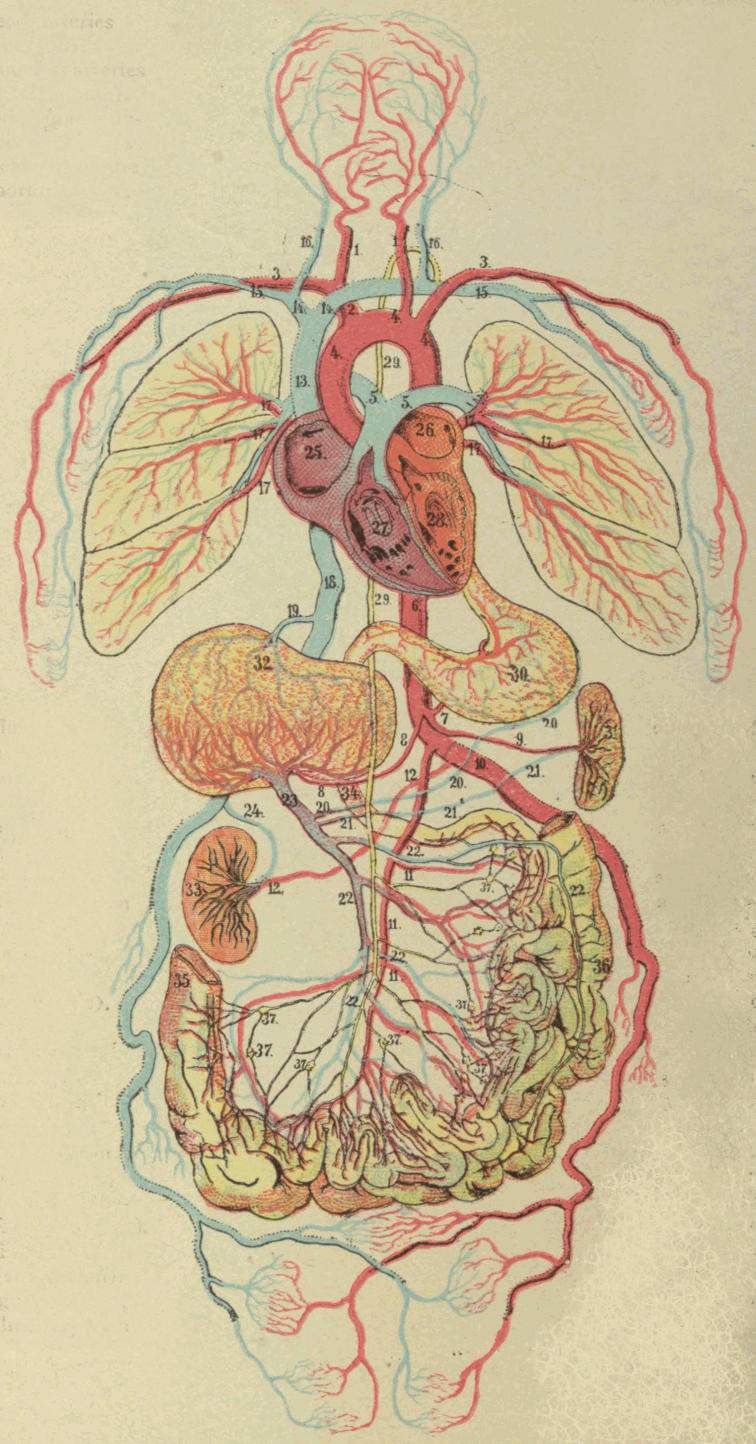

| V. | The Circulation | H 51 |